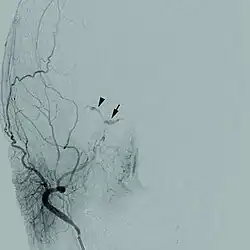

This is based on MRI scan, magnetic resonance angiography and CT scan. A cerebral digital subtraction angiography (DSA) enhances visualization of the fistula.

- High resolution digital subtraction angiography may help in classifying CCF into dural and direct type and thus formulate a strategy to treat it either by a balloon or coil or both with or without preservation of parent ipsilateral carotid artery.